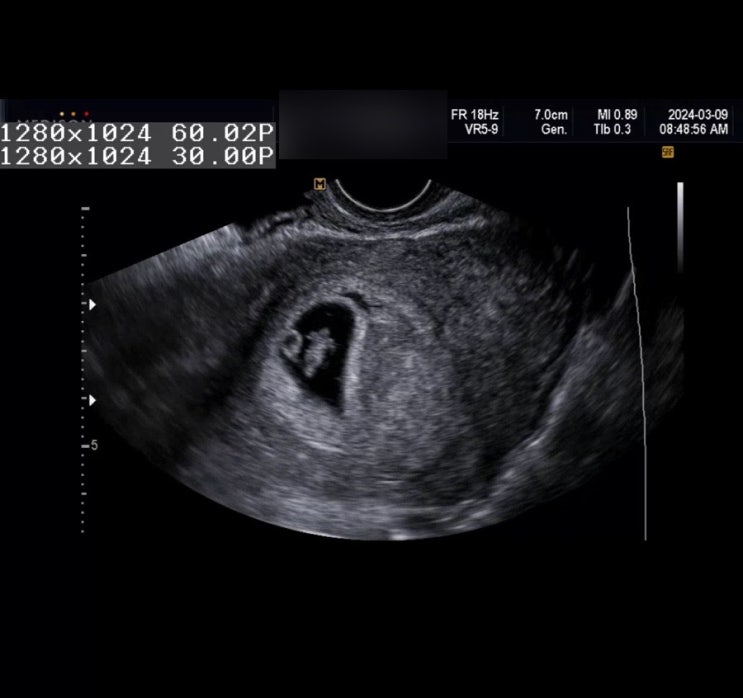

임신 7주차 - 12주차|임밍아웃 이벤트, 임신 초기 증상, 태명 짓기

임신일기 7주차 - 12주차 임밍아웃 이벤트 임신 초기 증상 태명 짓기 임신 확인 후에 회사에도 알리고, 슬...